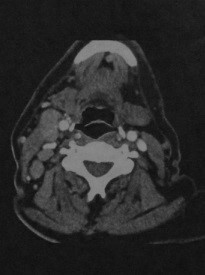

Метастазы. Пациент, страдающий раком языка. КТ в горизонтальной проекции: множественные увеличенные лимфатические узлы в нервно-сосудистом пучке шеи справа. Наблюдается вогнутость контура внутренней яремной вены и смещение грудино-ключично-сосцевидной мышцы кзади.

MPT, Т1 -взвешенное изображение во фронтальной плоскости (а): множественные увеличенные лимфатические узлы в правой половине шеи. Узлы имеют промежуточную или низкую интенсивность сигнала и расположены вдоль нервно-сосудистого пучка. Последовательность STIR (Ь): выраженное увеличение интенсивности сигнала в лимфатических узлах с метастазами в правой половине шеи.